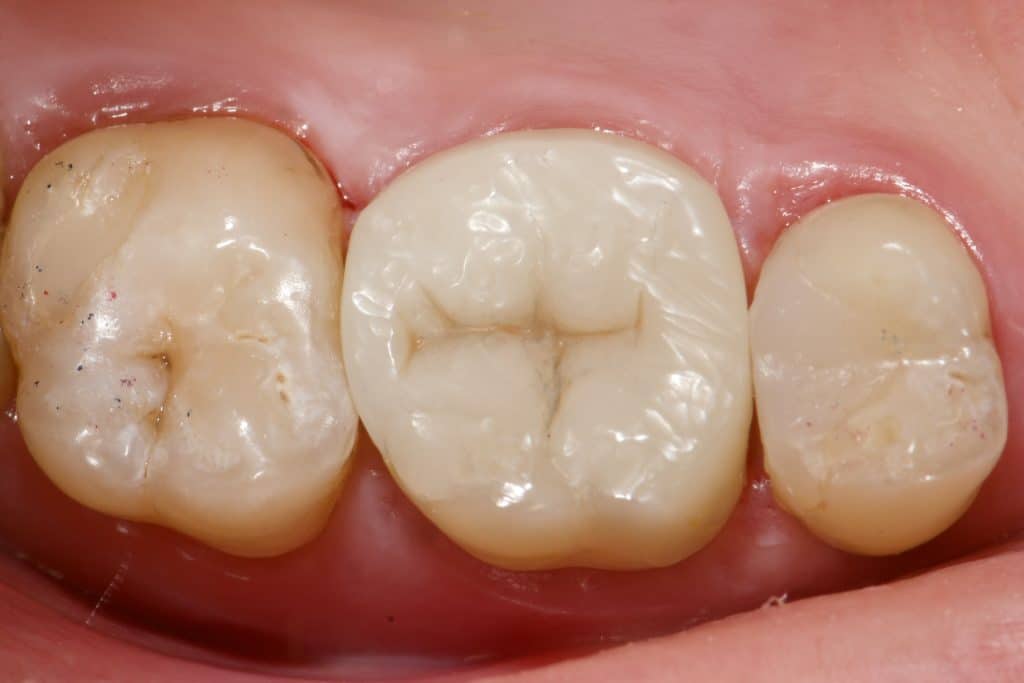

“Can a direct composite overlay function as effectively as an indirect lithium disilicate restoration? Composite restorations, once used as a long-term temporary solution for badly damaged molars, are now considered permanent. While the composite material remains the same, our understanding of its adhesive and physical properties has evolved. The procedure may be more time-consuming and require multiple stages in the same visit, depending entirely on the dentist’s skills.